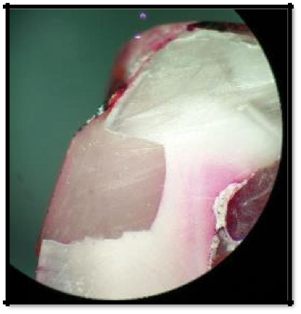

3. Penetration greater than one half of the length of occlusal/gingival wall (Figure 6)

Figure 6 Penetration greater than one half of the length of occlusal/gingival wall (Score 2).